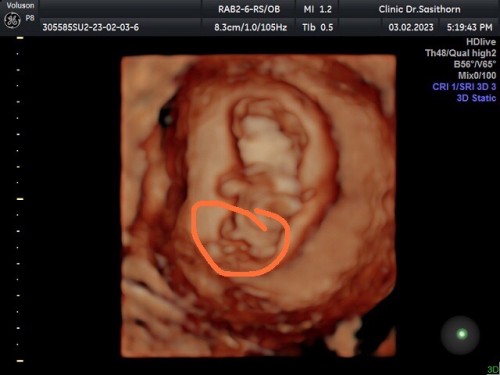

ที่วงกลม แม่ๆคิดว่าเป็นอะไรคะ สายสะดือ รึ ปิกาจู๋